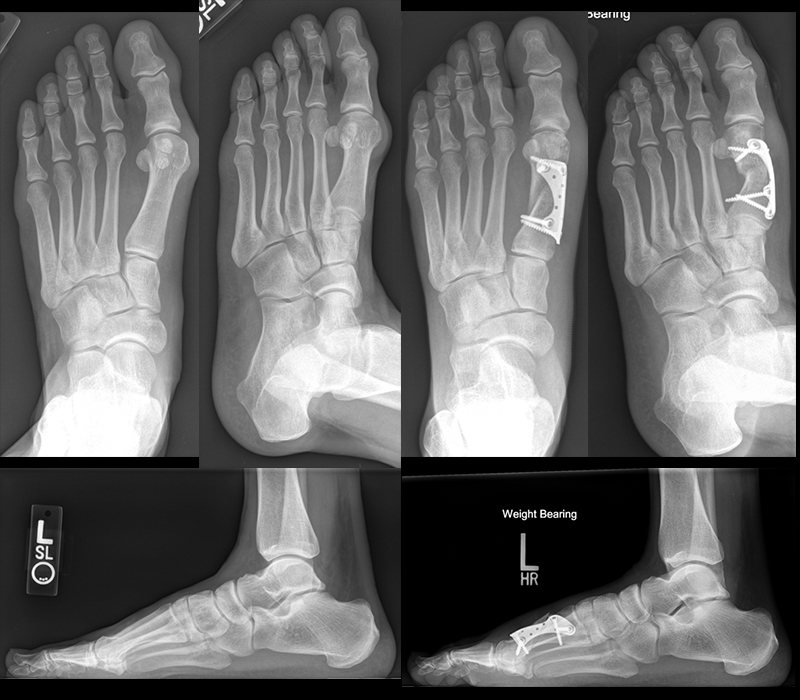

An erster Stelle der bildgebenden Diagnostik steht die konventionelle Röntgendiagnostik. Der betroffene Fuß wird dabei unter Belastung in 3 Ebenen dargestellt. Beurteilt werden der Intermetatarsale-I-Winkel (IM-Winkel), der Hallux valgus Winkel (HV-Winkel), die Lage der Sesambeine, der Arthrosegrad im MTP I Gelenk und ein mögliches plantares Klaffen „gapping“ im Tarsometatarsale-I Gelenk als Hinweis auf eine Gelenkinstabilität. Neben der reinen Beurteilung des Hallux valgus sollten immer auch die Kleinzehen beurteilt werden.

Zum Lesen der Bildbeschreibung und zur Vollansicht bitte das Bild anklicken. Bild: Markus Walther.

Die eigenständige Bewegung und Mobilisation im Großzehengrundgelenk und Interphalangealgelenk kann durch Physiotherapie, Lymphdrainage und Gangschule unterstütz werden. Eine radiologische Kontrolle erfolgt zur Dokumentation des Operationsergebnisses intraoperativ und nach 6 Wochen im Konfektionsschuh.